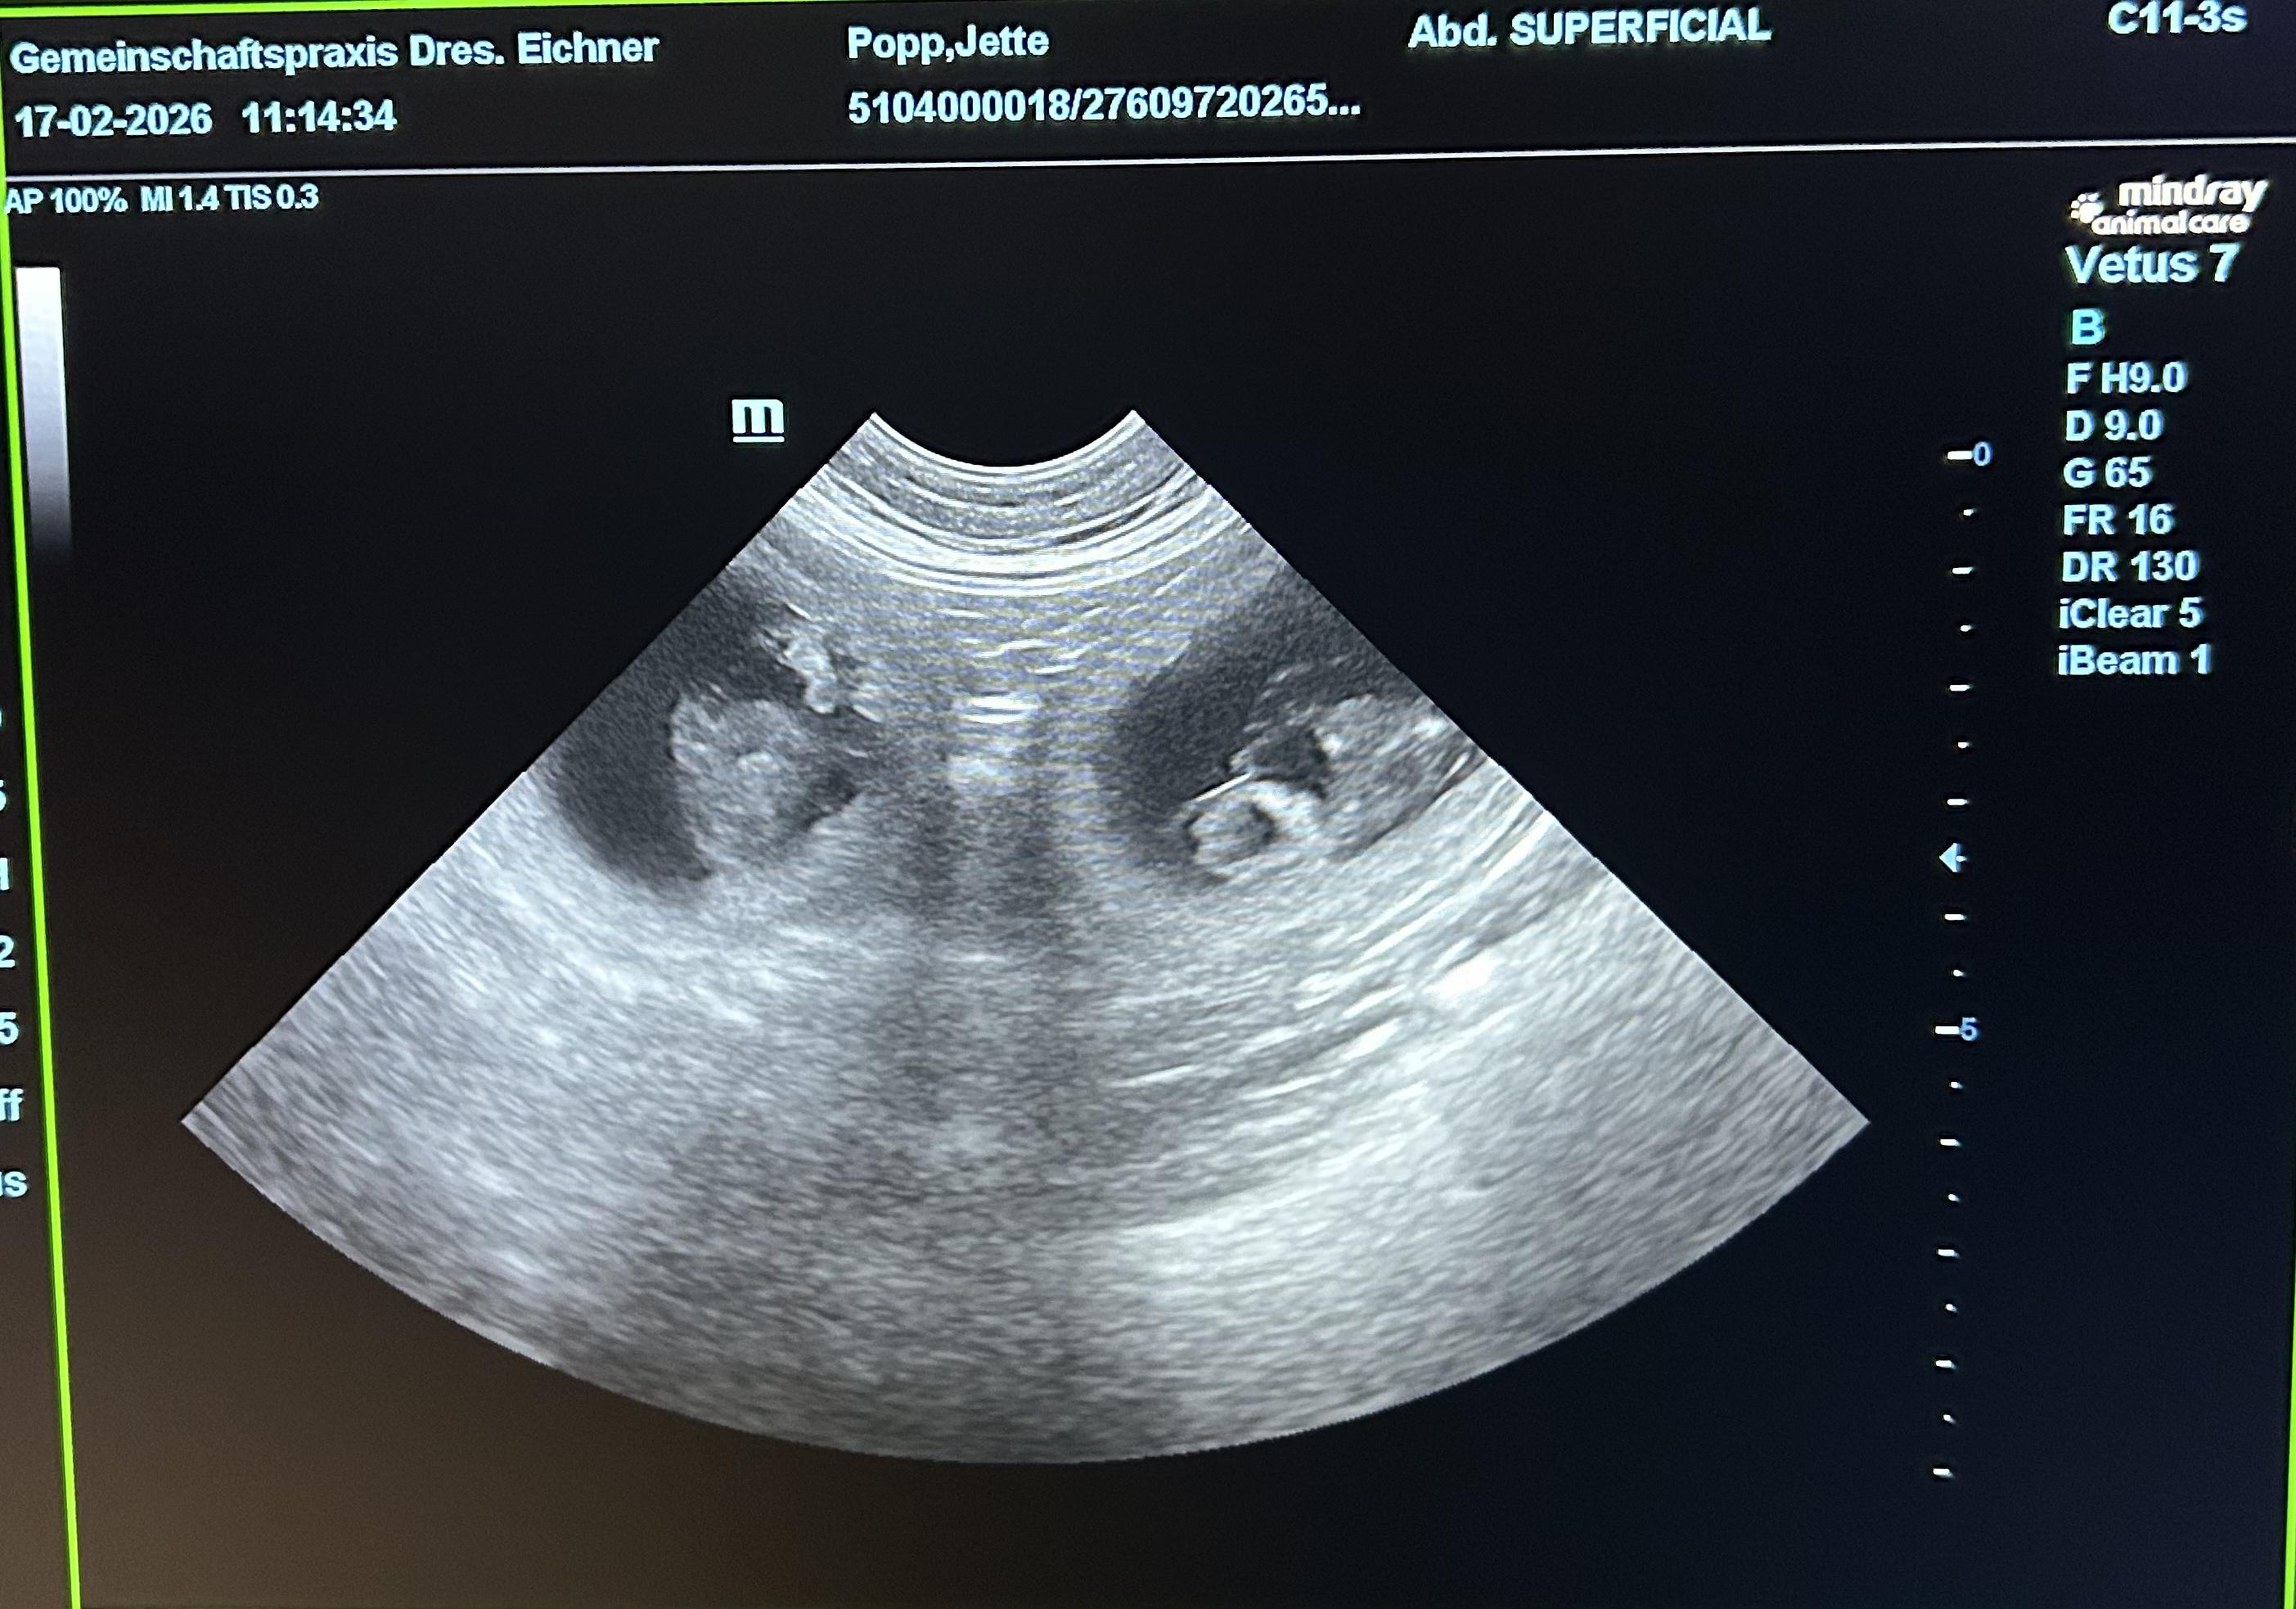

Jette hat 3 starke Jungs geboren